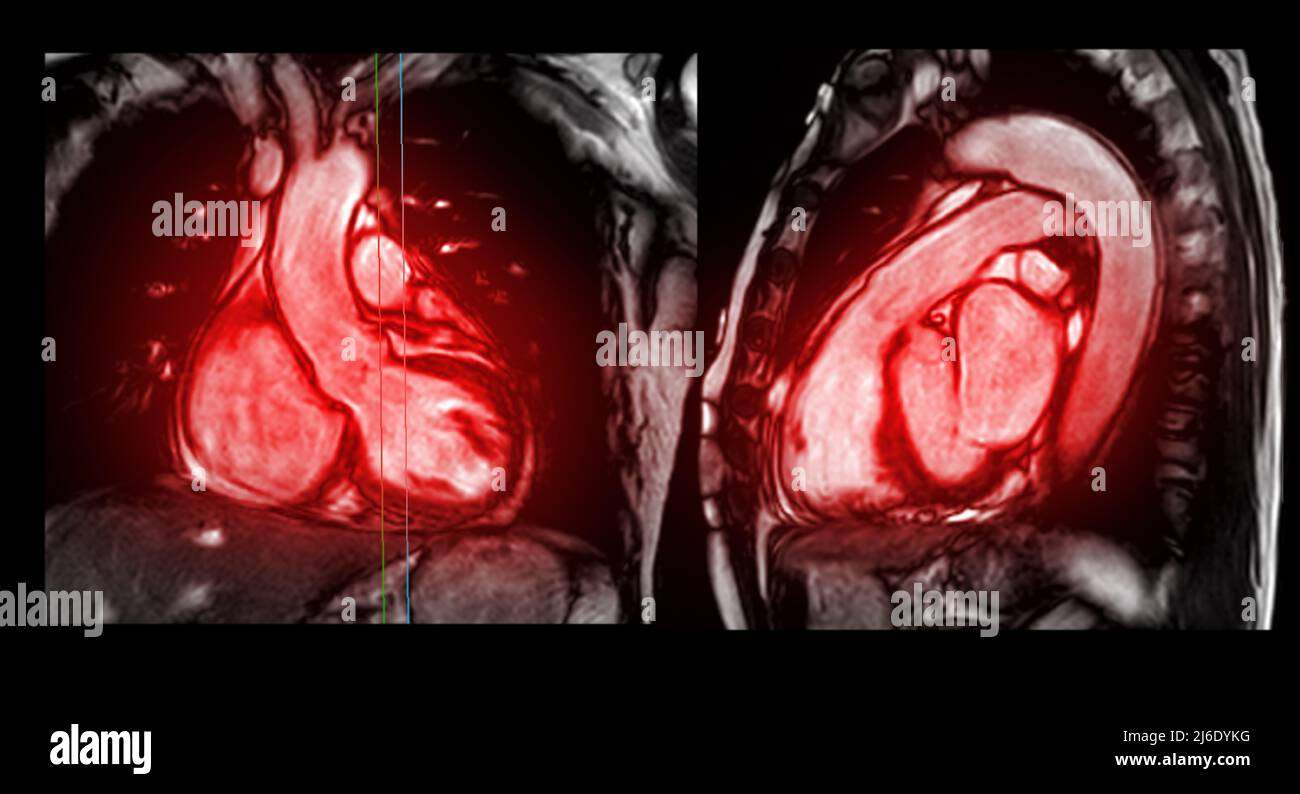

From www.alamy.com

MRI heart or Cardiac MRI ( resonance imaging ) of heart in What Is A Heart Mri Magnetic resonance imaging (mri) is a test that uses a large magnet, radio signals, and a computer to make images. An mri of your heart, sometimes called a mri heart scan, can show your heart’s structure and function—how well blood can flow. Cardiac magnetic resonance imaging (cardiac mri, cmr), also known as cardiovascular mri, is a magnetic resonance imaging (mri). What Is A Heart Mri.